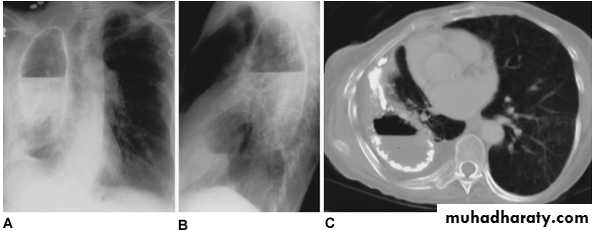

Tuberculous empyema. A and B. Posteroanterior and lateral chest x ray of a tuberculous empyema with calcified margins and an air fluid level. Aerated pulmonary parenchyma is visualized inferior to the empyema cavity. C. A midthoracic computed tomographic section demonstrates the calcified empyema cavity with an air fluid level. Although significant volume loss has occurred, a compressed aerated right lung without parenchymal destruction is seen.